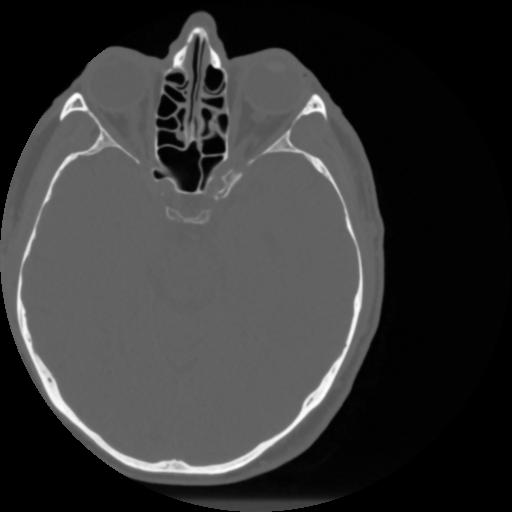

4 CEREBRO,,Vol,0.5,CEREBRO,,